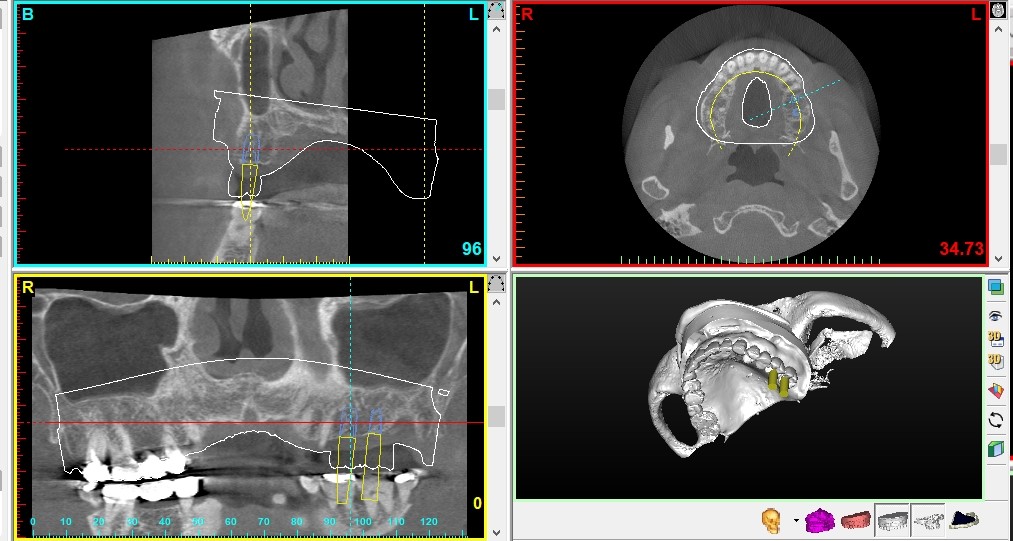

術前検査では、歯科用CT・3Dシミュレーション(Simplant)・サージカルステントです。

また、他にも歯周病や虫歯、噛み合わせのチェックなど、インプラントをより長く快適にお使いいただくための精密検査も行います。

CTを使いしっかりと治療計画がなされていないことによるミス、手術中に起こるリスクが最も大きなリスクとして存在します。この原因は、診査診断のミスであり、治療技術の不足です。

下顎の場合、下槽管という太い神経や血管がある部位があります。インプラント手術時、神経や血管を傷つけてしまい、神経麻痺などが起きるリスクがあります。

また上顎の場合、上顎洞と呼ばれる骨の空洞まで突き抜けてしまい、炎症を起こすケースも報告されています。

これらは、本来であればCTを用いてしっかりと血管や神経の位置を立体的に確認した上で、安全な位置と適切なインプラントを決定し、手術に当たらなければいけなかったところを怠った「人為的ミス」だと考えられます。